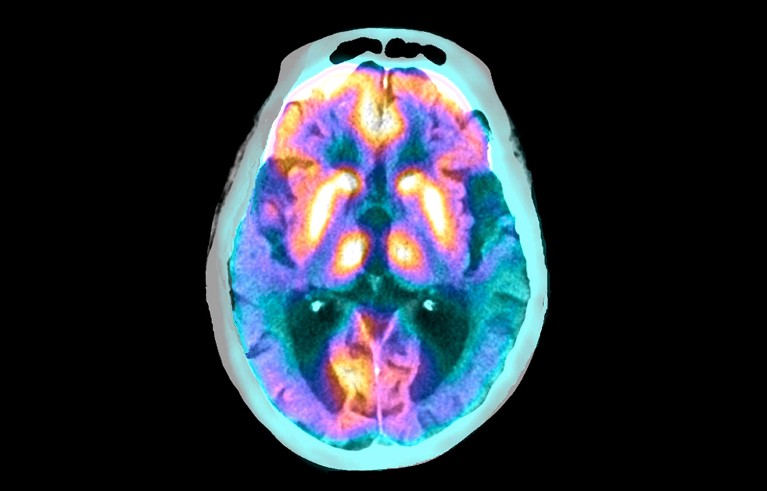

Credit: Zephyr/Science Photo Library

A group of specialized cells play a crucial part in clearing toxic proteins from inside the brain1. But in people with Alzheimer’s disease, these cells malfunction, leading to the build up of tau proteins — a hallmark of the disease.

Tanycytes, specialized cells that line the third ventricle of the brain, are unique because they are in direct contact with both the bloodstream and the cerebrospinal fluid (CSF). This means that they can circumvent the blood–brain barrier to allow molecules into and out of the brain. “Tanycytes are highways for the brain,” says Vincent Prévot, a neuroendocrinologist based in Paris at Inserm, the French National Institute of Health and Medical Research.